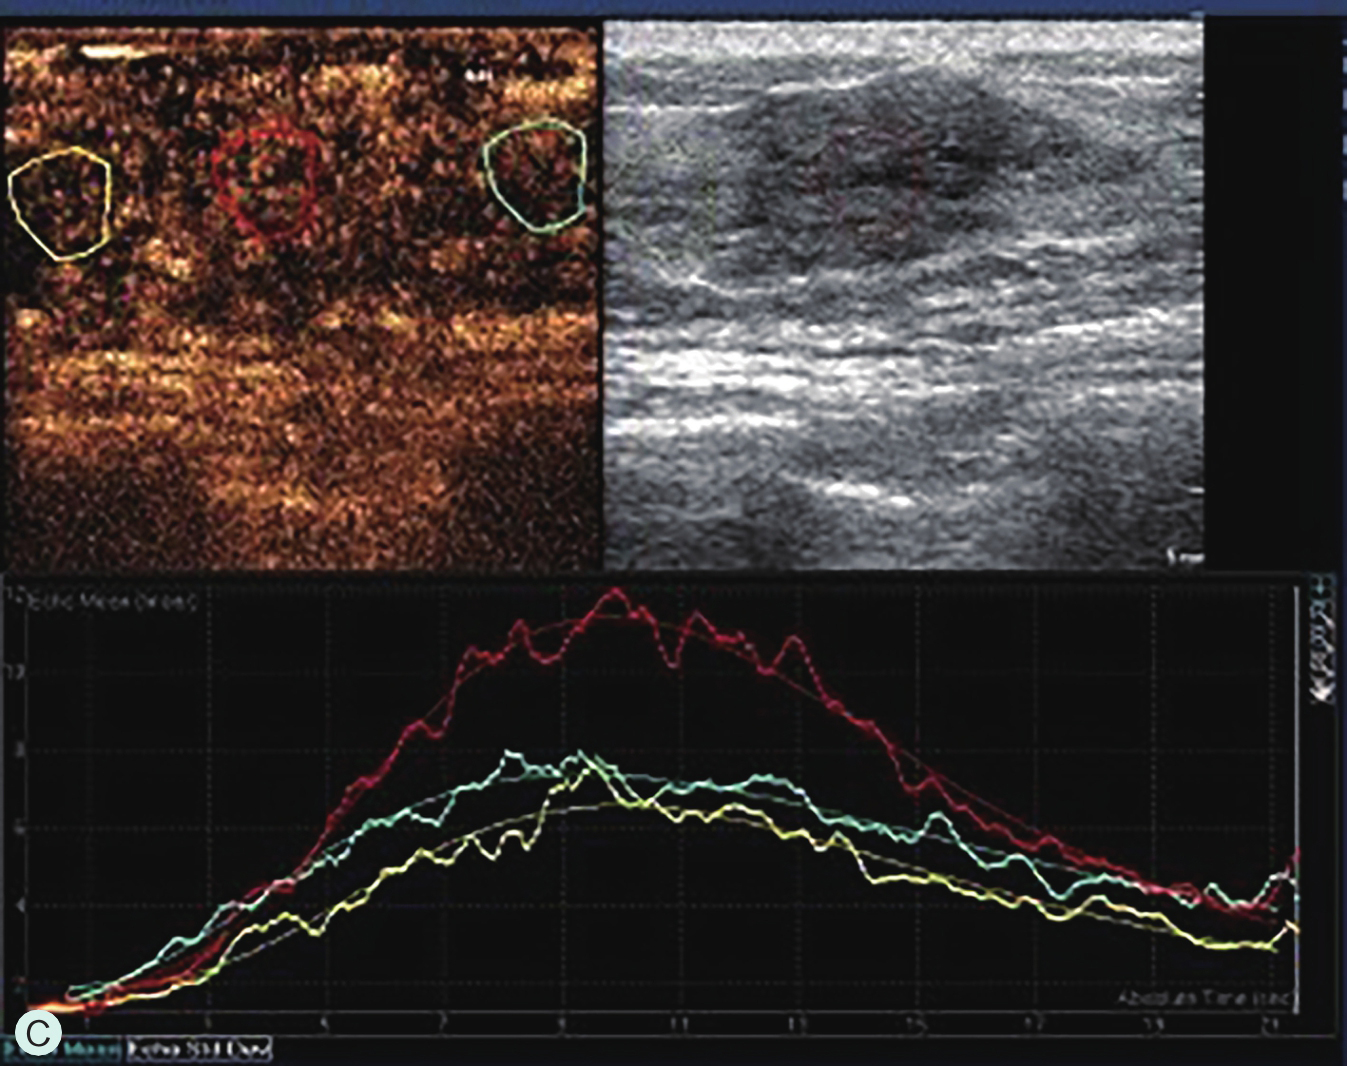

A.同步测量病灶大小与高增强范围;B.勾勒病灶与增强范围;C.定量分析

图2-2-11 乳腺肿瘤的微血管演进示意图

6.定量分析时,对不同区域分别取样,或包络整个病灶取样,所获得的时间-强度曲线参数也会出现差异,故取样时应尽可能包络病灶最大范围,并在病灶内及正常腺体以相同的感兴趣区面积多点取样进行相互比较,取样时应避开首先增强的滋养血管或无增强区,定量分析作为定性分析的辅助工具,应基于定性分析判读结果综合分析。